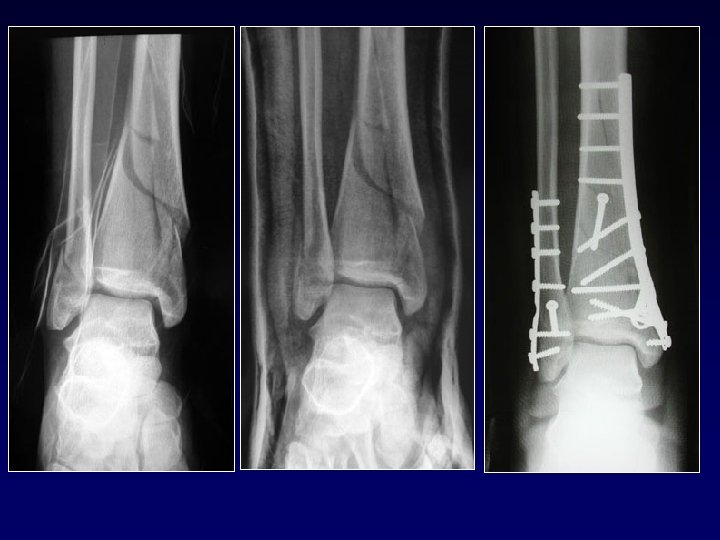

Fratture trasversali Frattura metafisaria bassa delle 2 ossa della gamba molto scomposta

Fratture meta-epifisarie